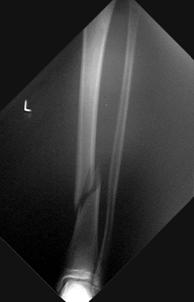

Fracturi simple: SPIRALA OBLICA TRANSVERSALA

Fractura spirala de Fractura transversa de diafiza femurala Fractura spirala de diafiza tibiala

diafiza humerala

Fractura spirala de diafiza tibiala Fractura oblica de diafiza tibiala Fractura transversala de diafiza tibiala